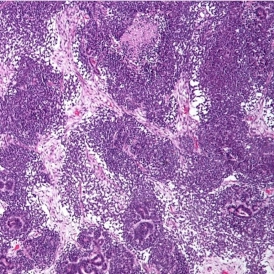

The IHC Tumor-Macrophages App provides tissue detection, including the separation of tumor and healthy tissue. It detects macrophages based on specific staining (e.g., CD68) and outputs the area of macrophages within tumor and healthy tissue.

Image: Courtesy of Dr. Patrick Michl, Dr. Maren Egidi, and Dr. Heidi Griesmann, Universitätsklinikum Halle (Saale).

App Category 3

The IHC Tumor Vascularization App provides tissue detection, including the separation of tumor tissue and tumor stroma (healthy tissue). Additionally, it detects blood vessels based on appropriate stains (e.g., CD31) and measures the number and area of these blood vessels. The vessel detection can also be programmed to close open stained vessel walls and to connect separated vessel sections within a definable distance. The App outputs the number, density, and areas of vessels within both tumor and healthy tissue.